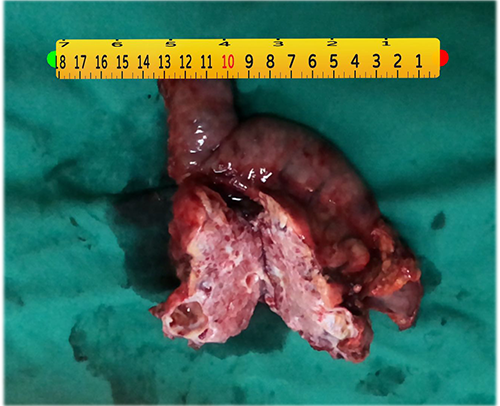

胰头囊腺瘤---胰十二指肠切除